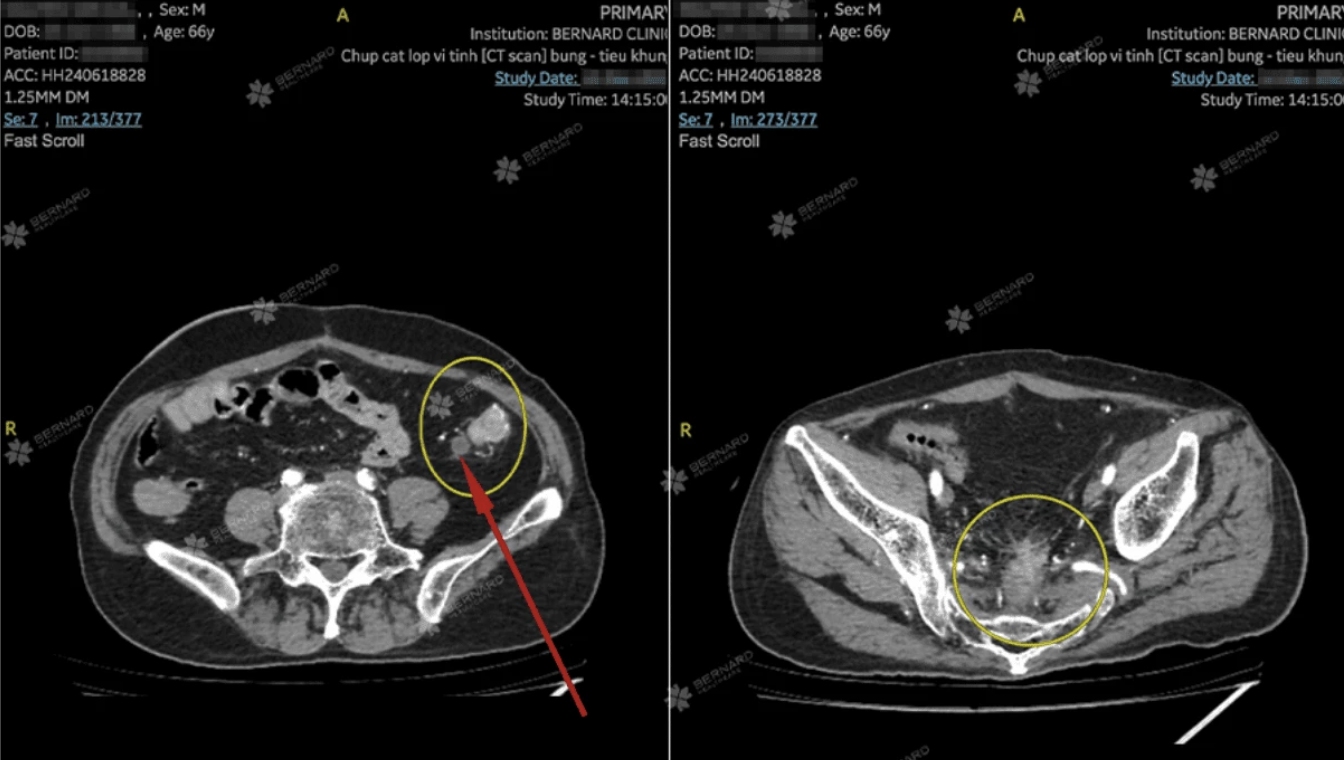

Hình ảnh học cho thấy vị trí nối sau phẫu thuật trực tràng: thành trực tràng dày bất thường, bờ không rõ, nghi ngờ tái phát ung thư trực tràng. Song song đó, đại tràng trái xuất hiện tổn thương dài 3,5 cm, dày nhất hơn 1 cm, kèm hạch vùng (dmax 8mm), nghĩ nhiều đến ung thư mới. Dù chưa ghi nhận xâm lấn cơ quan lân cận nhưng hình ảnh học thể hiện tính chất ác tính rõ rệt.